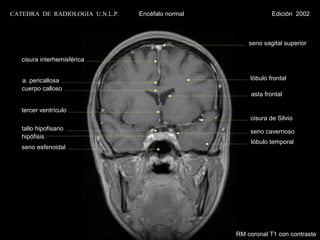

seno sagital superior

cisura interhemisférica

a. pericallosa                                      lóbulo frontal

cuerpo calloso

asta frontal

tercer ventrículo

cisura de Silvio

tallo hipofisario                                   seno cavernoso

hipófisis

lóbulo temporal

seno esfenoidal

RM coronal T1 con contraste